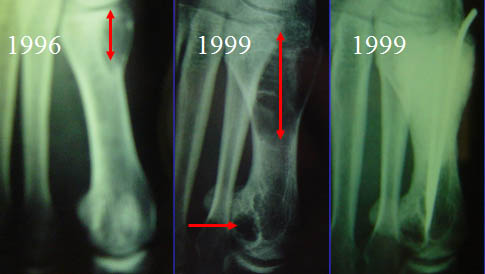

Une patiente de 17 ans consulte en 1996 pour lésions lytiques étagées du membre inférieur droit. Les lésions principales siègent sur la métaphyse fémorale inférieure droite et sur l'extrémité supérieure du tibia. Elles sont lytiques, légèrement soufflantes avec des cloisons de refend.

Elles s'accompagnent d'une lésion diaphysaire tibiale basse et d'une lésion du pied.

Le 17/07/1996 on réalise un curetage, une cryothérapie à l'azote liquide et un comblement au ciment des lacunes tibiales et fémorales menaçant de fracture.

En 1999, la lésion de l'orteil évolutives sur les radiographies successives et devenue douleureuse et traitée par comblement ciment.

Les lésions connues sont toutes stables voir régréssives, y compris celles qui n'ont pas été traitées.